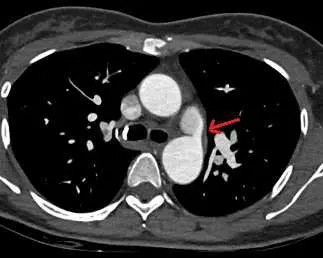

39歲女性,健康檢查時發現有心雜音,進一步做了電腦斷層檢查影像如附圖,最可能的診斷為下列何者?

本題核心在於胸部電腦斷層(CT)影像中,辨識主動脈與肺動脈間的異常交通(ductus arteriosus),與其他主動脈病變(pseudoaneurysm、aneurysm、coarctation)的影像表徵進行鑑別。

– 第一張圖為胸部橫截面動脈期增強CT,在左側肺動脈入口(red arrow)與降主動脈之間,可見一條細長、錐形的高密度血管通道,從降主動脈延伸至左主肺動脈,並於肺動脈端收細。此通道外壁平滑,無血栓或增厚壁層,連續性佳,形態符合典型Type A型PDA(conical ductus with prominent aortic ampulla) (radiopaedia.org)。